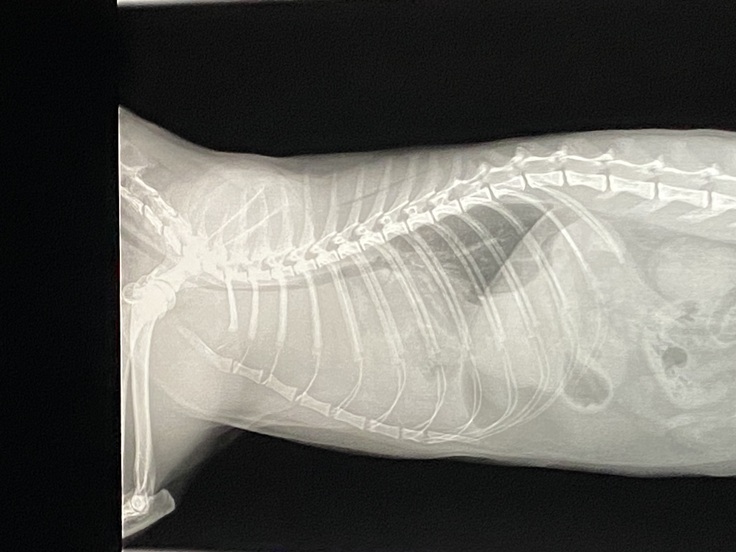

②画像は、胸水を抜いた後です。

全ての胸水は抜いていませんが、120cc抜いたとのことでした。心臓の下に3センチの腫瘍が見つかりました。